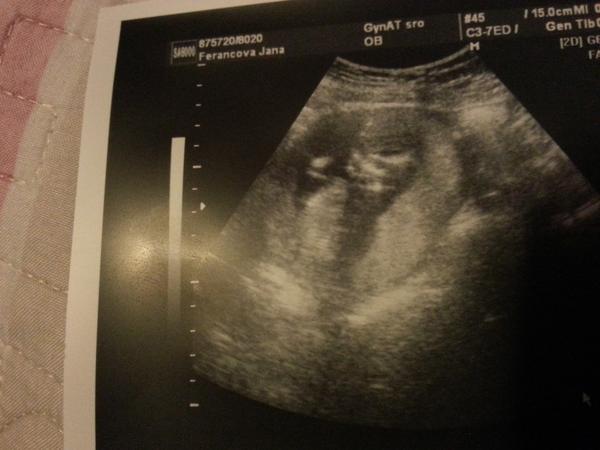

@uankab Ahoj Zuzi, cítim sa nanič, je mi brutálne zle, už asi tretí deň na skapanie, celý deň. Nemôžem nič jesť, zo všetkého ma naťahuje. Z nemocnice som sa vrátila vo štvrtok a v piatok som bola na kontrole u svojho gynekológa a ten povedal, že hematóm sa už vstrebal a bábätko krásne rastie a presne zodpovedá veľkosti podľa ovulky. Dnes som podľa menzesu 8+4 a podľa ovulky 8+5. Tak som veľmi šťastná, že to moje zlatíčko je v poriadku. 🙂

@jankaferancova Jani, krásne fotky, blahoželám k dobrým výsledkom, len nech ste zdravučkí 🙂